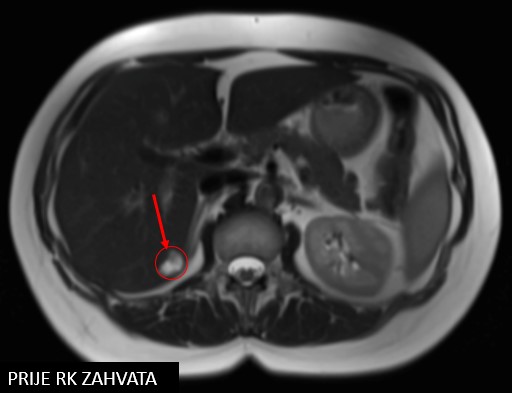

SABR meta hepatis et pelvis (21.11.2017.)

Rezultat – 47 mjeseci nakon RK

potpuni nestanak tretiranih lezija